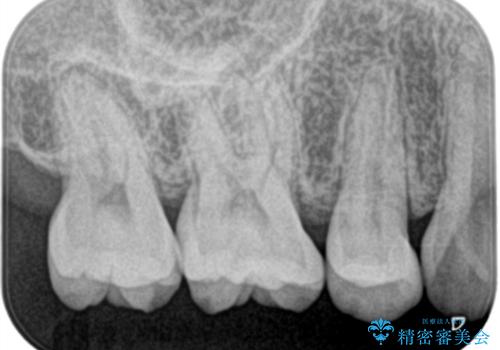

銀歯を除去し虫歯があるか確認し、虫歯がある場合は虫歯を取ってからセラミックが入るように形を作っていきます。

セラミックインレー(7万円)税別